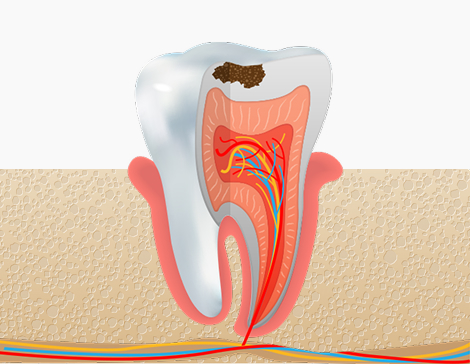

충치의 단계의 증상

충치 1단계

법랑질(치아의 가장 바깥층)

치료방법

레진치료 : 충치 부위를 제거하고 치아색 재료로 메움

충치 2단계

상아질 경계 또는 상아질층까지

인레이 / 온레이 치료 : 손상된 부위만 제거 후 부분 보철로 복원

충치 3단계

치수(신경)까지 진행

신경치료 후 크라운 보철 : 감염된 신경 제거 후 치아 전체 보강

충치 4단계

치근, 치조골·잇몸까지 진행

발치 및 임플란트 / 브릿지 : 염증 부위 제거 후 대체치료 진행